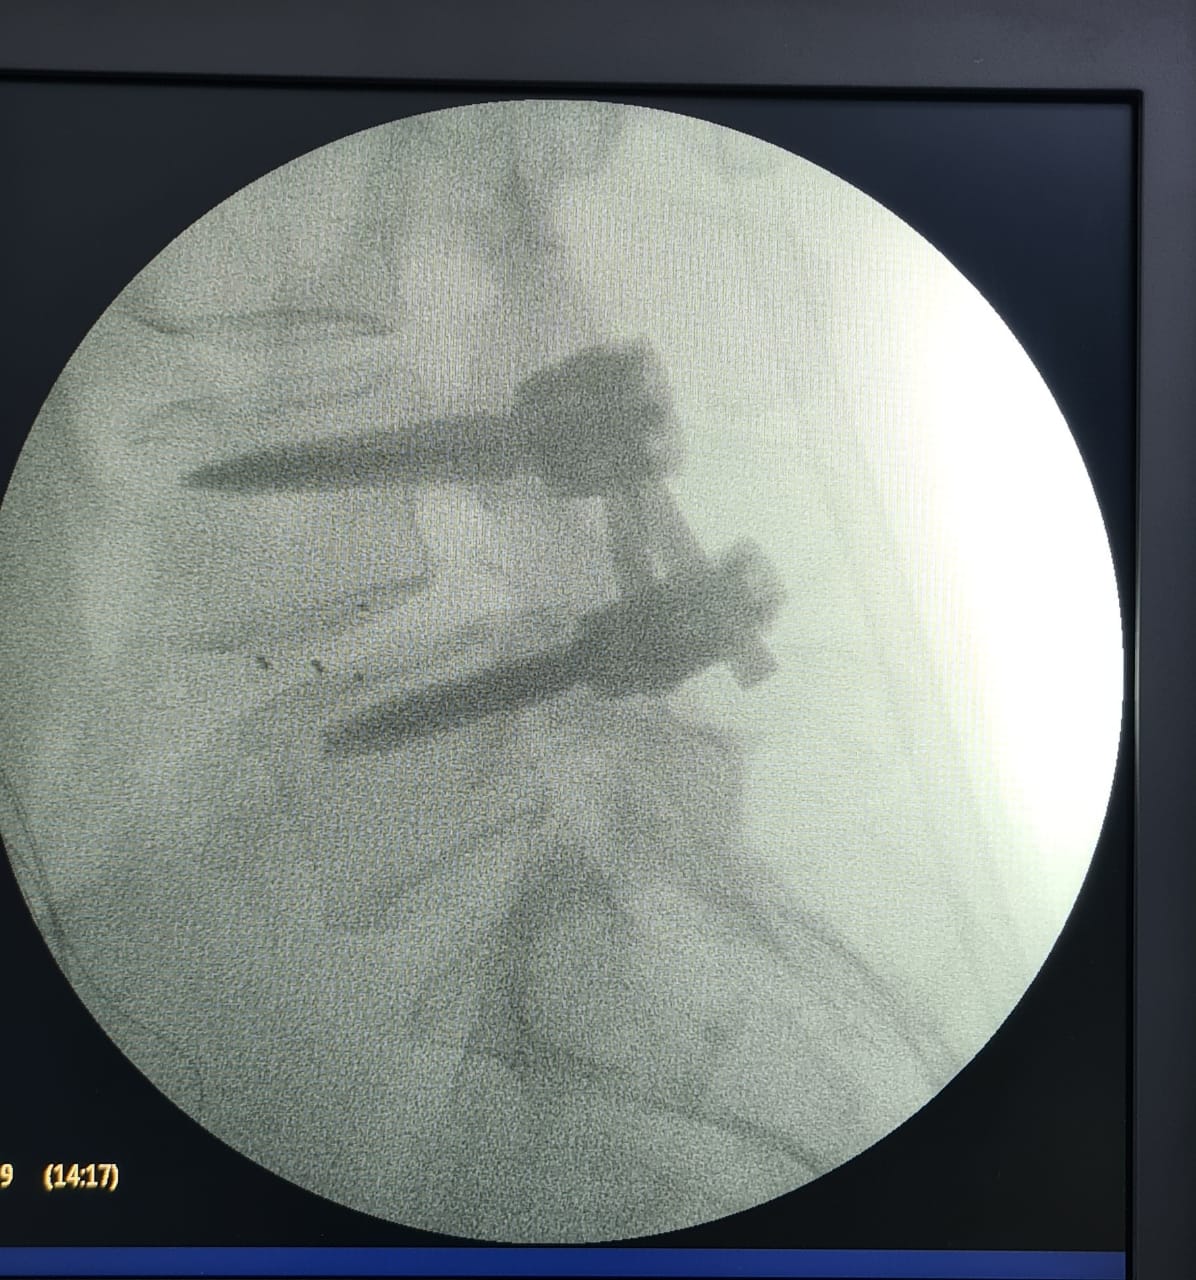

“Fueron tres tipos de exposiciones. Una de ellas es la cirugía en vivo, donde realizamos dos procedimientos en pabellón, acompañados por destacados especialistas, el Dr. Carlos Zanardi, presidente de la Sociedad de Neurocirugía de Buenos Aires, Argentina y el Dr. Cristiano Meneses, director del Instituto de Columna de Brasil”, precisó el Dr. Muñoz.

A continuación, compartimos las fotografías enviadas por el Dr. Avaria a la Sociedad de Neurocirugía de Chile: